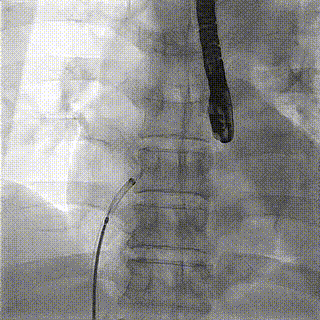

患者于2021年11 月5 日在全麻下进行心房分流器植入。术中右心导管测量肺动脉19mmHg,PCWP 16mmHg,右房压4 mmHg,平均压力梯度5 mmHg。手术中全麻下使用经食道超声确认房间隔穿刺部位在卵圆窝附近,穿刺成功后在送入加硬导丝轨道支撑。根据患者病情及血流动力学结果,使用6 mm球囊预扩张,选择孔径6 mm心房分流器植入,透视下测量分流孔径6mm,孔径精准达标。植入后即刻效果明显,左房负荷超载和肺淤血明显减轻,血流动力学指标改善。肺动脉压降低至18mmHg,PCWP降至6mmHg,右房压降至3 mmHg,平均压力梯度维持在3 mmHg。心房分流器植入部位准确,形态良好,效果理想,释放卸载分流器。

房间隔球囊扩张